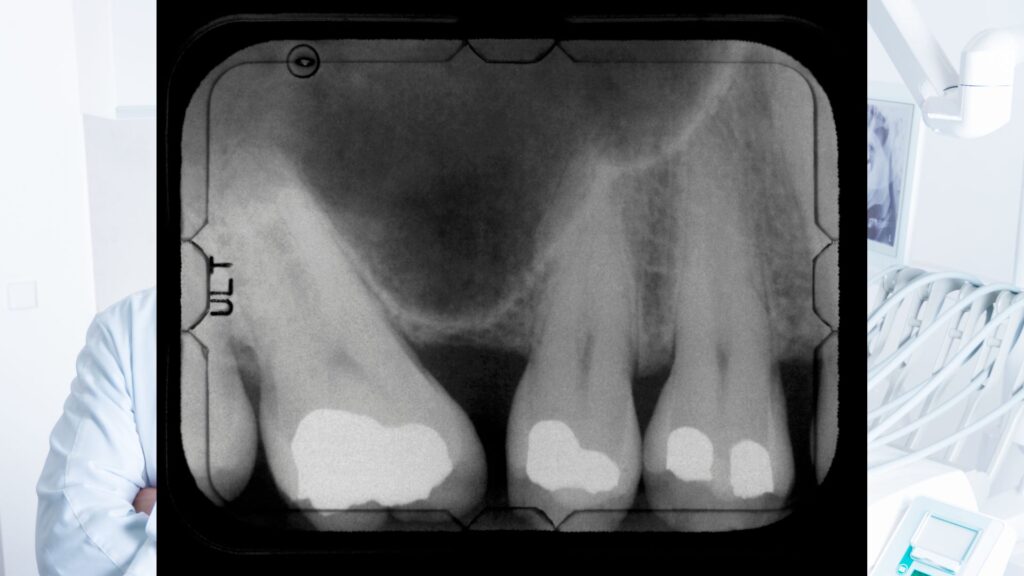

- ● デンタルレントゲン(部分撮影)

- 1本〜数本の歯を詳しく撮る検査です。

- 被曝量:非常に少ない

- 虫歯・根の治療の確認に使用

- 日常生活で受ける自然放射線と比べてもごくわずか